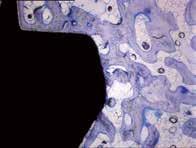

REM-Aufnahme der Oberfläche von BONITex® Osseointegration des mit BONITex® beschichteten Implantats.

Die bioaktive Oberfläche BONITex® zeichnet sich durch die Kombination einer gestrahlt, geätzten Oberfläche in Verbindung mit einer 2 Mikrometer dünnen und gleichmäßigen bioaktiven CaP-Schicht aus.

Die BONITex®-Beschichtung weist eine CaP-Schichtstärke von ca. 2 µ auf. Dadurch können die biologi schen Vorteile wie Osseointegrati on, Zellattraktion und verbessertes Attachment für die extrazelluläre Matrix ausgenutzt werden.

Mit den wahlweise zur Verfügung stehenden Oberflächen BONITex® und DUOTex wird eine sichere Oberflächenkonditionierung erzielt. BONITex® und DUOTex haben eine gestrahlt/geätzte Oberfläche. Im Implantathalsbereich wurde die Rauigkeit stark reduziert. Das fördert die Knochenanlagerung an Implantaten, die unter die Knochenlinie gesetzt wurden. Wenn über dem Knochen der Halsbereich des Implantats frei liegt, wird durch die reduzierte Rauhigkeit eine mögliche Ansiedlung von Bakterien verhindert. BONITex® besitzt eine zukunftsweisende Oberflä chenstruktur zur schnelleren Osseointegration und damit die Möglichkeit einer frühzeitigen prothetischen Versorgung. BONITex®-Implantate zeigen in einem frühen Stadium (zwischen 14 und 30 Tagen) im spongiösen Knochen eine hohe Knochenimplantatkontaktrate von durchschnittlich 80% (siehe Studie der FAU Erlangen).